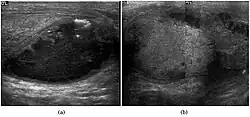

Seminoma is the most common tumor type in cryptorchid testes. The risk of developing a seminoma is increased in patients with cryptorchidism, even after orchiopexy. There is an increased incidence of malignancy developing in the contralateral testis too, hence sonography is sometimes used to screen for an occult tumor in the remaining testis. On US images, seminomas are generally uniformly hypoechoic, larger tumors may be more heterogeneous [Fig. 3]. Seminomas are usually confined by the tunica albuginea and rarely extend to peritesticular structures. Lymphatic spread to retroperitoneal lymph nodes and hematogenous metastases to lung, brain, or both are evident in about 25% of patients at the time of presentation.

Embryonal cell carcinoma

Embryonal cell carcinomas, a more aggressive tumor than seminoma usually occurs in men in their 30s. Although it is the second most common testicular tumor after seminoma, pure embryonal cell carcinoma is rare and constitutes only about 3 percent of the nonseminomatous germ cell tumors. Most of the cases occur in combination with other cell types. At ultrasound, embryonal cell carcinomas are predominantly hypoechoic lesions with ill-defined margins and an inhomogeneous echotexture. Echogenic foci due to hemorrhage, calcification, or fibrosis are commonly seen. Twenty percent of embryonal cell carcinomas have cystic components. The tumor may invade into the tunica albuginea resulting in contour distortion of the testis [Fig. 4].